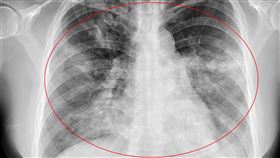

大白肺害大S猝逝!醫:被痰液淹到無法呼吸

大S因感染流感併發肺炎猝逝,引發外界對肺炎的關注。醫...

2025/02/05 11:27

肺炎死者解剖:氣道和肺部損傷為主

中國專家解剖武漢肺炎患者遺體發現,病毒主要引起深部氣...